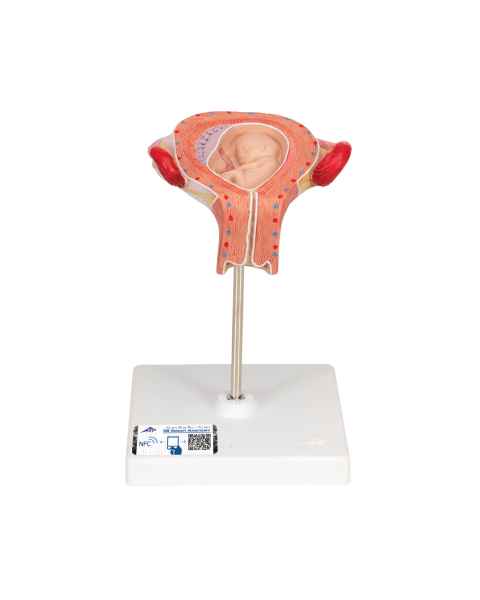

Female anatomical models are an ideal teaching aid to help educate both students and patients. Our extensive selection of female anatomy models includes female pelvic models, pregnancy series models, pelvis skeleton models, delivery/childbirth simulators, clinical breast trainers and self-exam models, uterus/ovary models, and more. Teaching simulators and self-exam models are excellent for educating students and patient education.

For example, the Wearable Breast Self-Exam Model can be easily worn, in order to better train and practice breast self-examination. Our line of prevention and detection models includes the Realistic Left Breast Model, Uterus/Ovary Model with Pathologies, Model of the Female Breast, and the Clinical Breast Trainer. Obstetricians will benefit from owning female anatomy figures of uteri and pelvises with fetuses inside, as well as sets of models that demonstrate the stages of fertilization. Women, particularly first-time mothers, will appreciate having a female education model that clearly illustrates the pregnancy process and what exactly is occurring inside of their body.